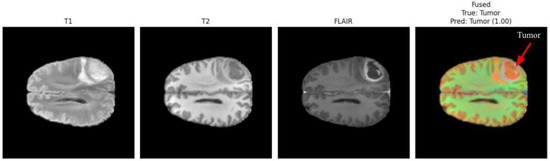

Figure 3 and Figure 4 present a visual comparison of the individual MRI modalities (T1, T2, FLAIR) and their fused representations used as inputs to the proposed multimodal CNN. Each modality contributes distinct and complementary tissue contrasts, while the fused image integrates these characteristics to enhance tumor visibility and support accurate detection. Arrows in the fused images highlight the regions identified as tumorous by the classifier, demonstrating the system’s ability to localize pathologies with high confidence.

T1-weighted images offer high anatomical detail, providing sharp structural boundaries useful for identifying mass effects and tissue displacement. T2-weighted images emphasize fluid accumulation and edema, capturing peritumoral changes. FLAIR suppresses cerebrospinal fluid signals, increasing contrast around lesions located near ventricles and cortical sulci. The fused representation consolidates these complementary features into a single enhanced image, improving tumor delineation and facilitating more reliable classification.

In Figure 4, the fused image again highlights a distinct tumor region, and the model assigns a prediction confidence of 1.00. This case demonstrates the robustness of the multimodal fusion approach across varying tumor locations, contrast profiles, and patient characteristics [5,32]. The improvement in lesion conspicuity achieved through multimodal fusion supports reliable detection even when individual MRI sequences provide insufficient, ambiguous, or incomplete diagnostic information.

The differing confidence scores (0.98 and 1.00) correspond to different patients and tumor presentations. Such variability is expected due to the heterogeneity of brain tumors, differences in imaging quality, and variations in lesion size or contrast. Overall, these visual analyses underscore the effectiveness of multimodal MRI fusion in enhancing tumor localization cues that guide the proposed CNN-based detection system.

Figure 4. Multimodal fusion example from a second patient case. The fused image effectively enhances pathological features across modalities, with the arrow indicating the localized tumor area [5,32]. The model predicted tumor presence with a confidence score of 1.00.